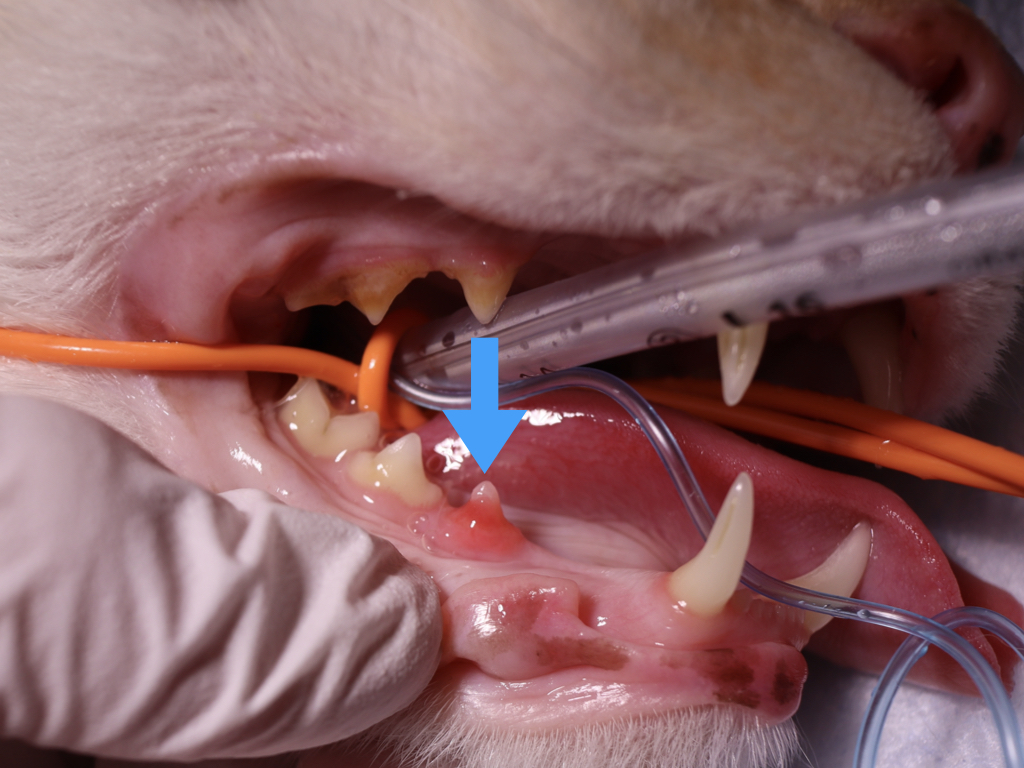

猫の吸収病巣は、猫の虫歯とも呼ばれています。

詳しい原因はわかっていませんが、実は猫の20〜67%が罹患しているというデータがあります。

臼歯に現れることが多く、見た目として歯にかぶさるようなピンク色の歯肉が特徴的です。

もしこのピンク色を見つけたら、動物病院を受診し適切な検査や治療を行いましょう。